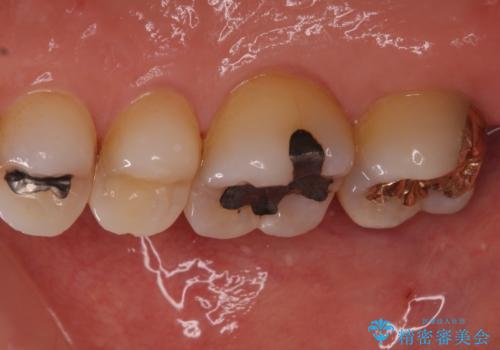

- 奥歯に装着されてい銀歯の中が虫歯になってしまったとのことで来院された患者様です。

虫歯をしっかりと取り除き、ゴールドインレー(PGAインレー)にて修復することとしました。